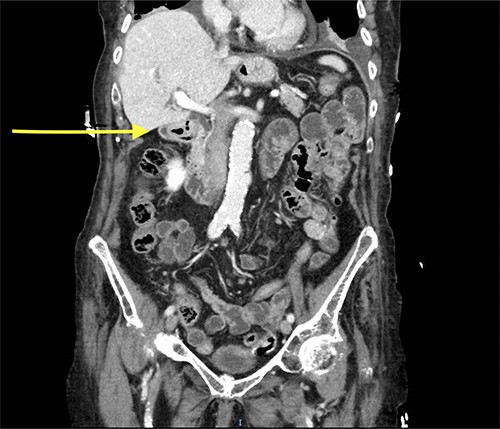

Abdominal CT scan showed a small intussusception involving the pylorus of the stomach and the first part of the duodenum with approximately 18-mm segment of the pylorus telescoping into the first part of the duodenum. This, however, did not cause a significant obstruction to the gastric outlet and the stomach was collapsed. No lead point mass or lesion identified within the limitations of the study.

The rest of the duodenum and small bowel loops are unremarkable (Figs 1 and 2).